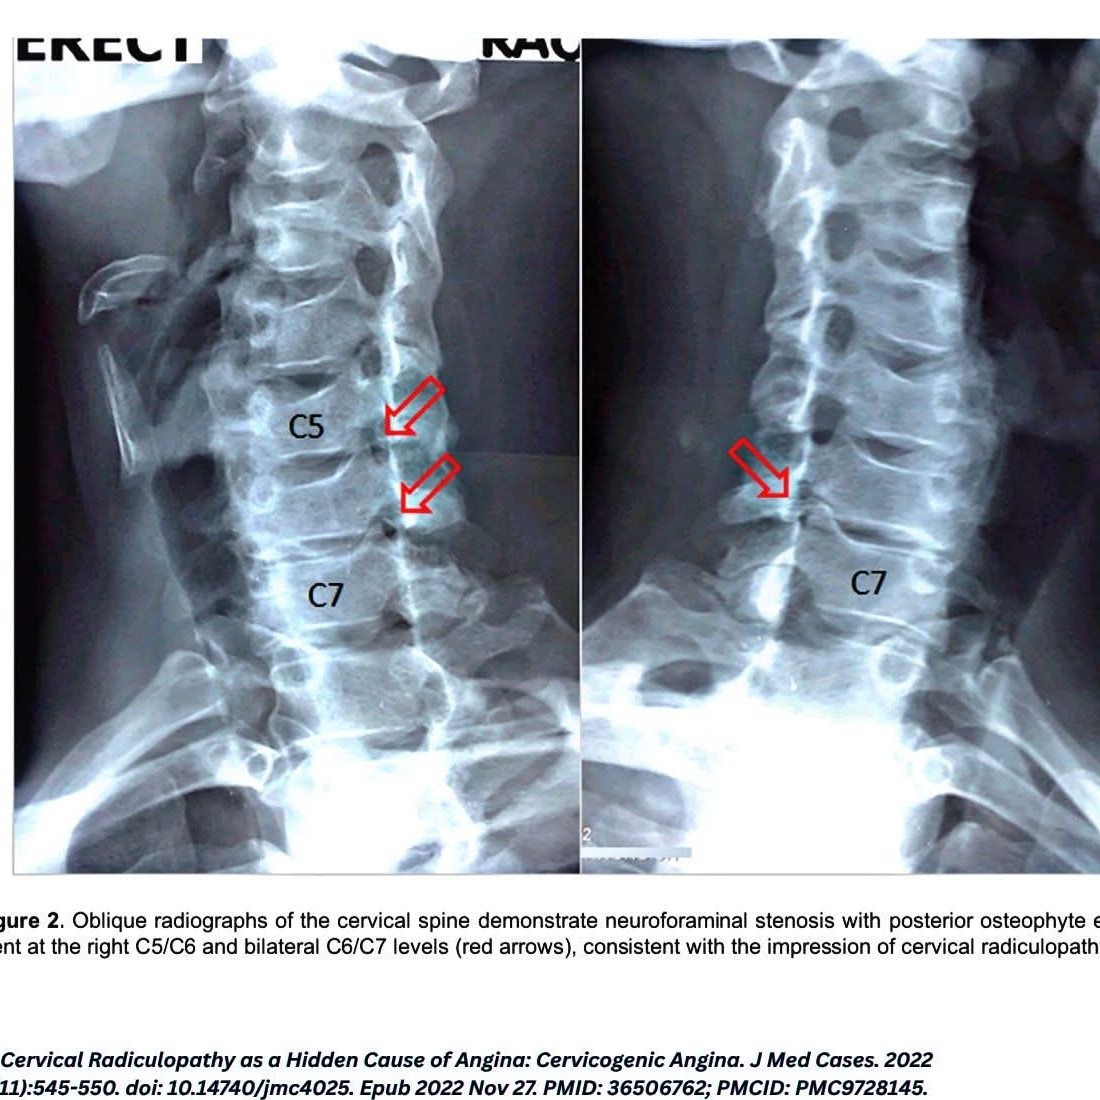

Cervicogenic Angina (CA): When Chest Pain Hides in the Neck